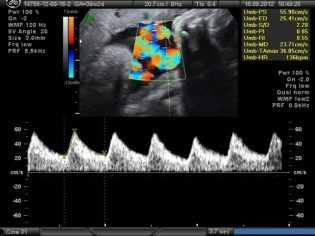

Так как через пуповину проходят кровеносные сосуды, то для оценки интенсивности кровотока врачи прибегают к назначению еще одного диагностического метода — допплерографии. Это обследование позволяет оценить, присутствуют ли какие-то дефекты кровоснабжения плаценты и организма плода. От того, как прикреплена пуповина к плаценте, во многом зависят и возможные осложнения.

Первородящая Щ., 26 лет (репродуктивный анамнез не отягощен), обратилась для планового осмотра в рамках раннего пренатального скрининга в сроке 12 +6 нед. Сканирование проводилось при трансабдоминальном и трансвагинальном доступе. При эхографии выявлено: размеры плода соответствовали сроку гестации: КТР плода 62 мм, БПР 18 мм, ОЖ 60 мм, толщина воротникового пространства 1,8 мм, длина носовой кости 2,3 мм. ЧСС плода 157 в минуту, ритм правильный. Диаметр желточного мешка 6 мм. Плацента располагалась по передней стенке матки, без особенностей размеров и структуры. Прикрепление пуповины к плаценте центральное. Экзоцеломическая полость не определялась. При допплерометрии выявлено отсутствие диастолического компонента кровотока в d. venosus и пуповине. У плода выявлен асцит (рис. 1). Ультразвуковых данных о ВПР плода не обнаружено. На расстоянии 4 мм от передней брюшной стенки плода визуализировалось гетерогенное образование с четкими ровными контурами округлой формы диаметром 25 мм (рис. 1-4), связанное с пуповиной, сложной эхоструктуры, представленное анэхогенным толстостенным включением, окруженным линейными септами повышенной эхогенности. В режиме ЦДК в выявленном образовании пуповины регистрировались единичные цветовые локусы (рис. 3, 4).